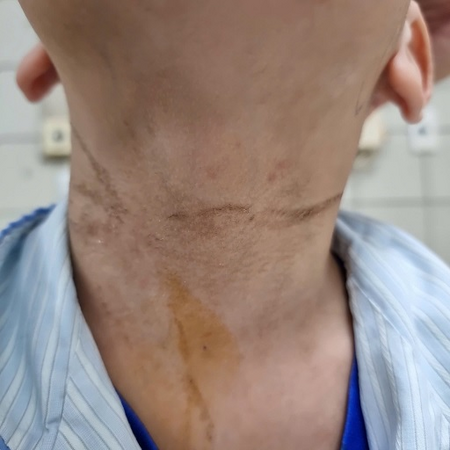

Hình ảnh vết dây thắt ở cổ bệnh nhi

Hình ảnh vết dây thắt ở cổ bệnh nhi

Ngay trong ngày, bệnh nhi được chuyển lên Trung tâm Nhi khoa, Bệnh viện Bạch Mai để tầm soát các nguy cơ tổn thương não, phù não, tăng áp lực nội sọ, suy tuần hoàn, hô hấp do thắt cổ, ngạt thở. Thời điểm tiếp nhận ở Trung tâm Nhi khoa, Bệnh nhi hôn mê, bóp bóng qua nội khí quản, xuất huyết dạng chấm rải rác vùng đầu mặt và có vết lằn đường kính 0,5cm dài 25 cm ở vùng cổ trước.

Ngay trong ngày, bệnh nhi được chuyển lên Trung tâm Nhi khoa, Bệnh viện Bạch Mai để tầm soát các nguy cơ tổn thương não, phù não, tăng áp lực nội sọ, suy tuần hoàn, hô hấp do thắt cổ, ngạt thở. Thời điểm tiếp nhận ở Trung tâm Nhi khoa, Bệnh nhi hôn mê, bóp bóng qua nội khí quản, xuất huyết dạng chấm rải rác vùng đầu mặt và có vết lằn đường kính 0,5cm dài 25 cm ở vùng cổ trước.